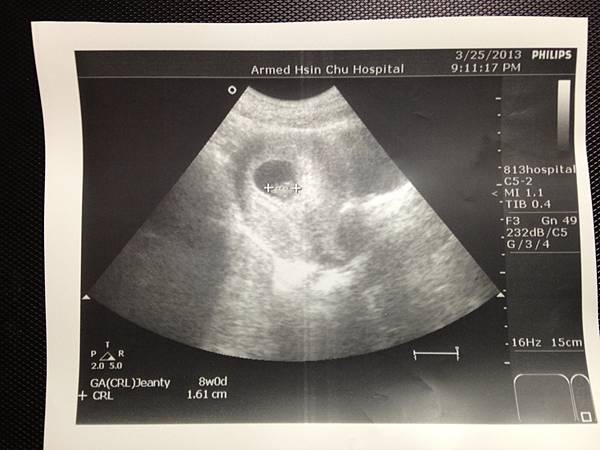

(20130325)

(怎麼還是顆蛋呢~ )

你現在有1.6cm嚕~

心跳178下, 大約是8週~

差不多差不多, 果然真的只是我生理期不準而已~ 斜率是對的就好:D